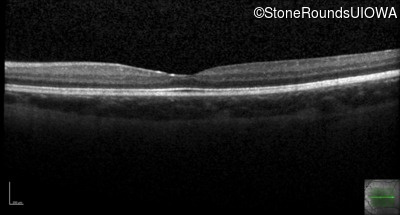

XL Retinoschisis (IIIB1)

XL Retinoschisis (IIIB1)

This 6 year old boy first experienced difficulty reading and seeing the blackboard at age 5.

| XL Retinoschisis | RS1 | Pro192His CCC>CAC | XL |